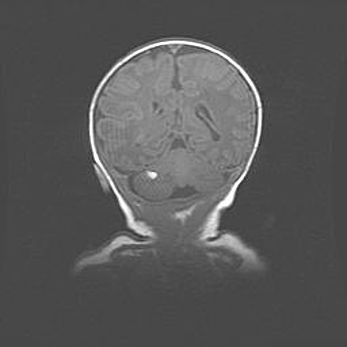

Множественные кисты обоих полушарий головного мозга, наибольшая из них в правой затылочной области. Ассиметричная атрофическая гидроцефалия.

Возраст: 7 месяцев

Вес: 5660 г

Пол: мужской

Окружность головы: 41,5 см

Срок гестации: 28-29 недель

Кисты головного мозга развиваются в результате многоочаговых некрозов вещества мозга и возникают вследствие перенесенной перинатальной инфекции, менингитов, энцефалитов, асфиксии, родовой травмы, расстройств мозгового кровообращения различного генеза. Образованию кист в веществе головного мозга плодов и новорожденных способствуют такие факторы, как высокое содержание в нем воды, недостаточная (или отсутствие) миелинизация и слабая астроглиальная реакция на повреждение.

Кисты могут сочетаться с гидроцефалией и другими поражениями головного мозга.